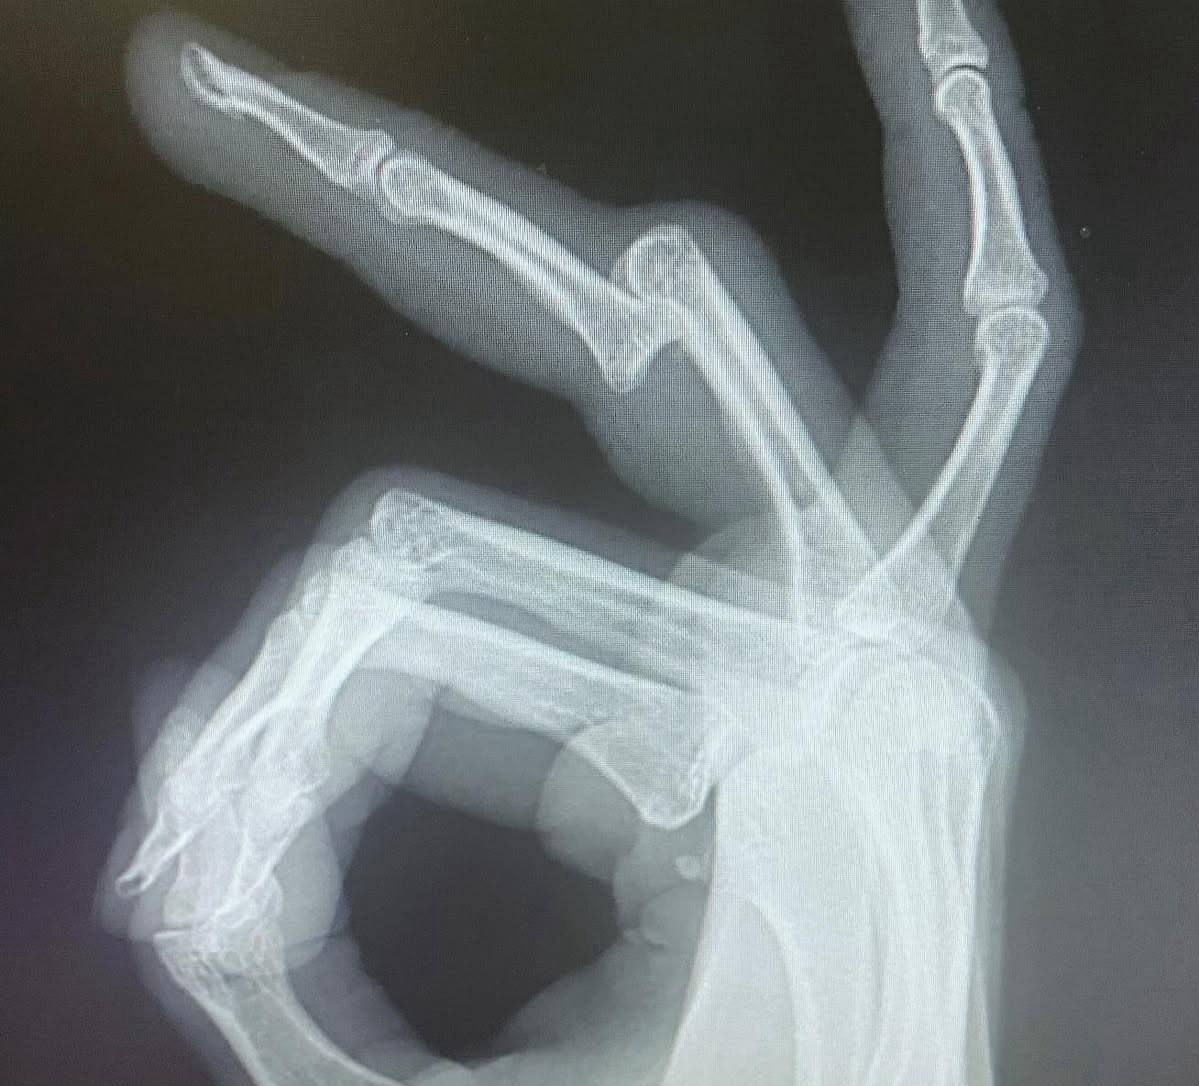

В результате этого происшествия у Вероники множество побоев и переломанные пальцы

рентген пальцев Вероники